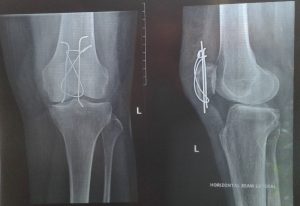

Marion walked into PPS Physiotherapy Kellyville in February 2017 after fracturing her Left patella (knee cap) tripping over at home in late 2016. She underwent surgery to have a wire threaded through the patella to assist in the fracture healing.

In March 2017, Marion’s progressed plateaued due to the surgical wire limiting her ability to move and at times it would catch in the knee causing her considerable pain. The surgeon agreed to remove this wire, a few months earlier than desired, to reduce the pain and increase her function. At the same time, a small non-harmful lump was removed from the right knee which we commonly referred to as ‘Lawrence the lump’…so maybe we should make that 3 surgeries now!